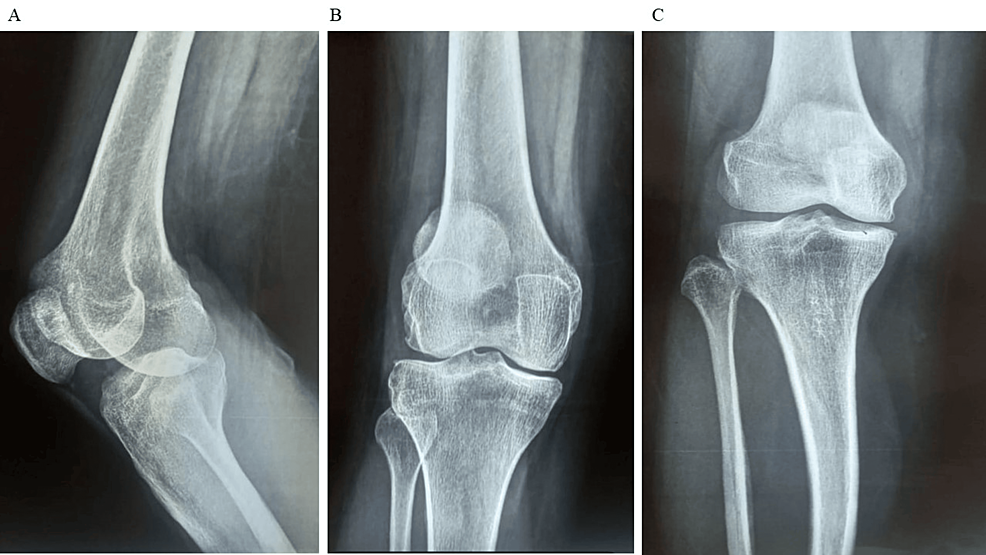

除了骨關(guān)節(jié)炎外,15名參與者還被發(fā)現(xiàn)患有骨缺損,占該隊(duì)列的30%。這些缺損包括各種情況,例如骨折、退行性骨病或先天性畸形,突顯了研究中涉及的骨科問(wèn)題多種多樣。下圖1顯示了開(kāi)始干細(xì)胞治療之前的骨骼側(cè)視圖和前后視圖。